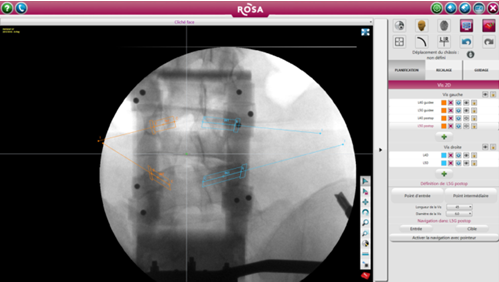

ROSA 是一種影像導(dǎo)航設(shè)備,直接根據(jù)術(shù)中放射線圖像上確定的標(biāo)志或使用導(dǎo)航指針定位工具。引導(dǎo)是基于術(shù)中2D圖像處理軟件完成的軌跡規(guī)劃,隨后患者俯臥位完成注冊(圖1)。在手術(shù)開始時,沿著患者的右手邊放置機(jī)器人,確保機(jī)器人的手臂能充分地覆蓋兩個節(jié)段(圖2)。然后外科醫(yī)生站在患者的另一邊。手術(shù)室的組織結(jié)構(gòu)圖如圖3所示。

圖1術(shù)前X線透視下椎弓根螺釘?shù)囊?guī)劃